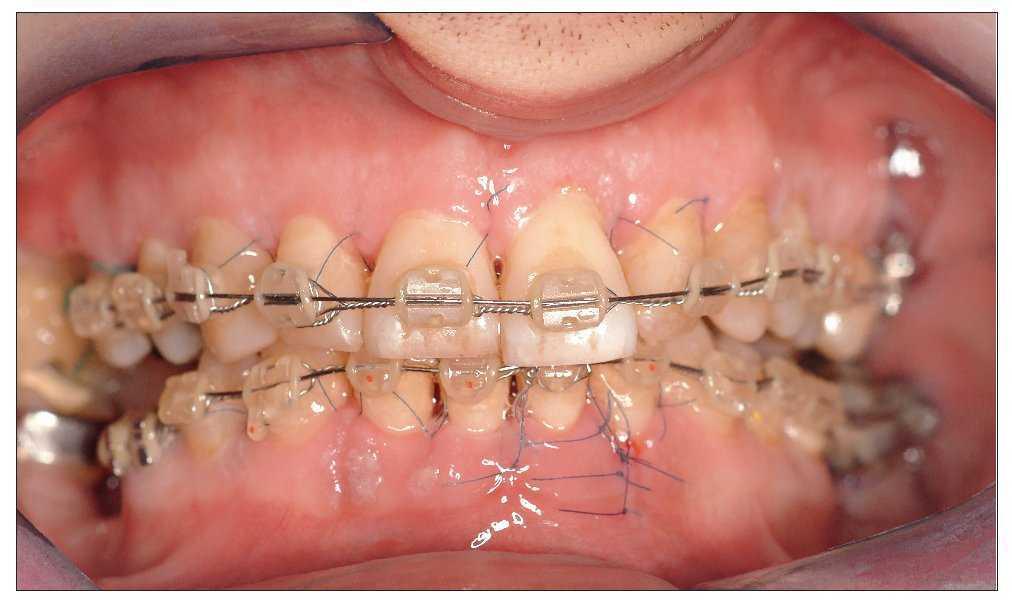

En la interconsulta ortodóncica se llegó a la conclusión de que era posible corregir con ortodoncia las malposiciones mediante aparatología multibandas después de un tratamiento periodontal regenerador eficaz. El objetivo de la corrección era lograr la intrusión del diente 21 elongado y el enderezamiento del diente 37 inclinado hacia mesial para obtener una normooclusión y colocar un futuro implante en la región del 36. Por medio de las fuerzas ortodóncicas intermitentes se pretendía aprovechar los efectos sinérgicos del tratamiento regenerador y del tratamiento ortodóncico para generar nuevas inserciones en el maxilar y en la mandíbula. Para la ferulización se colocaron los brackets de la aparatología multibandas 10 días antes de la intervención. En la mandíbula se colocó el arco para ferulizar el diente 31 con movilidad no fisiológica antes de la intervención, mientras que en el maxilar el arco no se colocó hasta el primer día del postoperatorio para asegurar un mejor campo visual y un mejor acceso durante la intervención quirúrgica (fig. 3).

Figura 3. Los brackets de la aparatología multibandas se colocaron 10 días antes de la intervención quirúrgica periodontal regeneradora. En la mandíbula, el arco para la estabilización intraoperatoria se encuentra colocado en el momento de la intervención, mientras que en el maxilar no se colocó hasta un día después de la intervención para no interferir en el campo quirúrgico.